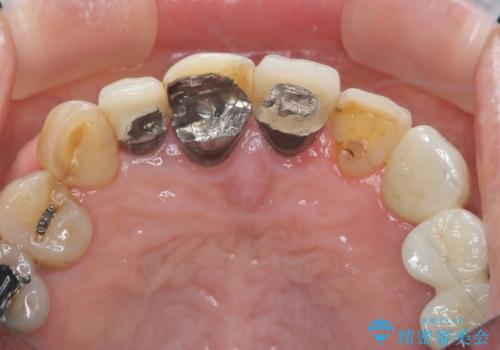

1. ぐらつく前歯 ブリッジ治療の治療前